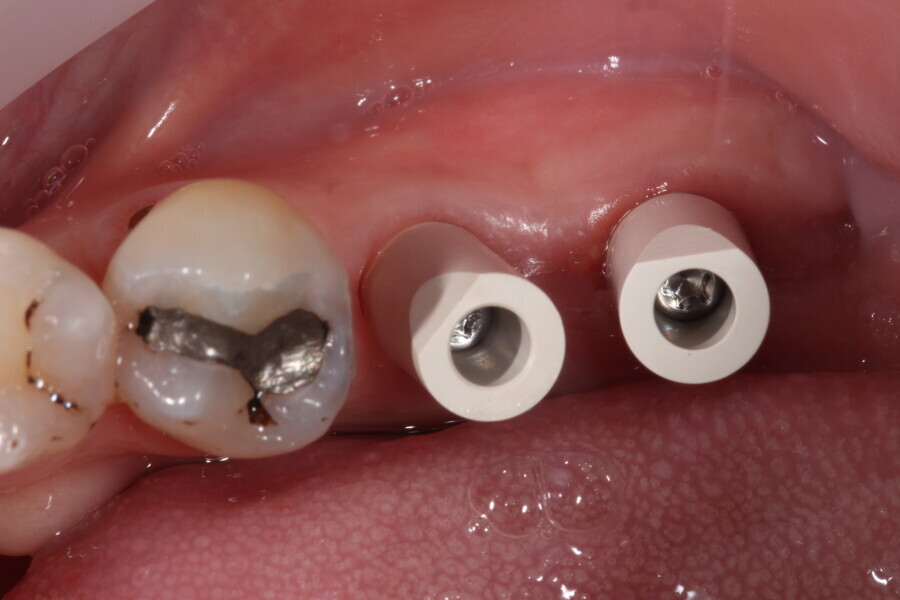

Fig. 10: Scanbodies in situ.